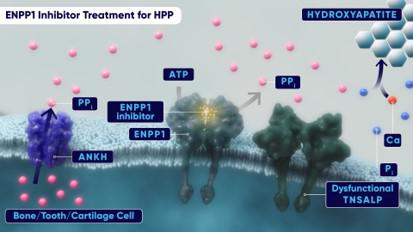

In July 2019, we formed a joint venture with Exscientia Limited ("Exscientia"), an Oxford, UK-based artificial intelligence ("AI") and machine learning drug discovery company with a proprietary chemical design platform to discover novel small molecule drug candidates. Exscientia was acquired by Recursion Pharmaceuticals, Inc. ("Recursion") in 2024 and we have continued work with Recursion on the discovery of a small molecule targeting an Ectonucleotide Pyrophosphatase/ Phosphodiesterase 1 ("ENPP1") inhibitor for the treatment of HPP. HPP is a rare, genetic disease characterized by mutations in the ALPL gene. The ALPL gene provides instructions for making an enzyme called tissue-nonspecific alkaline phosphatase, which plays an important role in the growth and development of bones and teeth. The incidence of HPP has been reported to be 1 in 100,000 to 1 in 300,000 (United States and Canada) for severe disease and 1 in 6,370 (European Union) for less severe forms. These mutations lead to diminished activity of the alkaline phosphatase enzyme and the accumulation of inorganic pyrophosphate (“PPi”), which inhibits bone mineralization causing multiple skeletal pathologies. We believe that a small molecule inhibitor of ENPP1 has the potential to bring meaningful benefit to HPP patients by reducing excess levels of pyrophosphate, thereby removing an inhibitor of calcium mineralization and bone formation.

In 2024 we presented data at the American Society for Bone and Mineral Research ("ASBMR") from an early lead ENPP1 inhibitor, REV101, in a mouse model of later-onset HPP demonstrating a 30% reduction in PPi, a key biomarker that is elevated in HPP and contributes to poor bone mineralization. Together with Recursion, we also advanced REV102, an ENPP1 inhibitor for the treatment of patients with HPP to position the molecule for additional preclinical development activities in 2025.